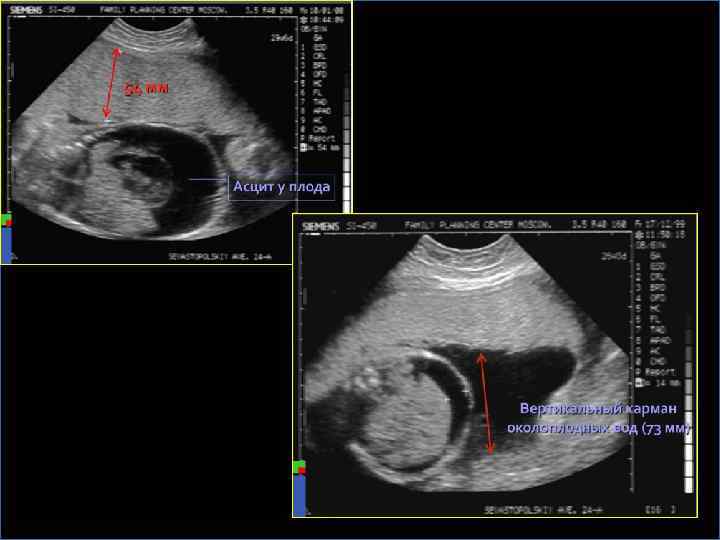

УЛЬТРАЗВУКОВАЯ ДИАГНОСТИКА Ранние признаки иммунной водянки плода – многоводие, гепатоспленомегалия, генерализованный отек При выраженной водянке плода: § Гидроперикард § Асцит и гидроторакс в сочетании с многоводием – очень неблагоприятный прогностический признак § Кардиомегалия § Отек кожи головы и конечностей § Плохая сократимость и утолщение стенки желудочков сердца § Увеличение эхогенности кишечника из-за отека его стенок § Гипертрофированная плацента, гомогенность плаценты § Необычная поза плода - «поза Будды» - позвоночник и конечности отведены от раздутого живота § Снижение двигательной активности

УЛЬТРАЗВУКОВАЯ ДИАГНОСТИКА На тяжесть гемолитической болезни плода указывают следующие результаты измерения структур плода: § § § Диаметр вены пуповины Вертикальный размер печени Толщина плаценты Увеличение скорости кровотока в нисходящей части аорты Пиковая систолическая скорость кровотока в средней мозговой артерии плода До обнаружения нарушений состояния плода динамический ультразвуковой контроль проводится еженедельно, при выявлении поражения плода – ежедневно или через день